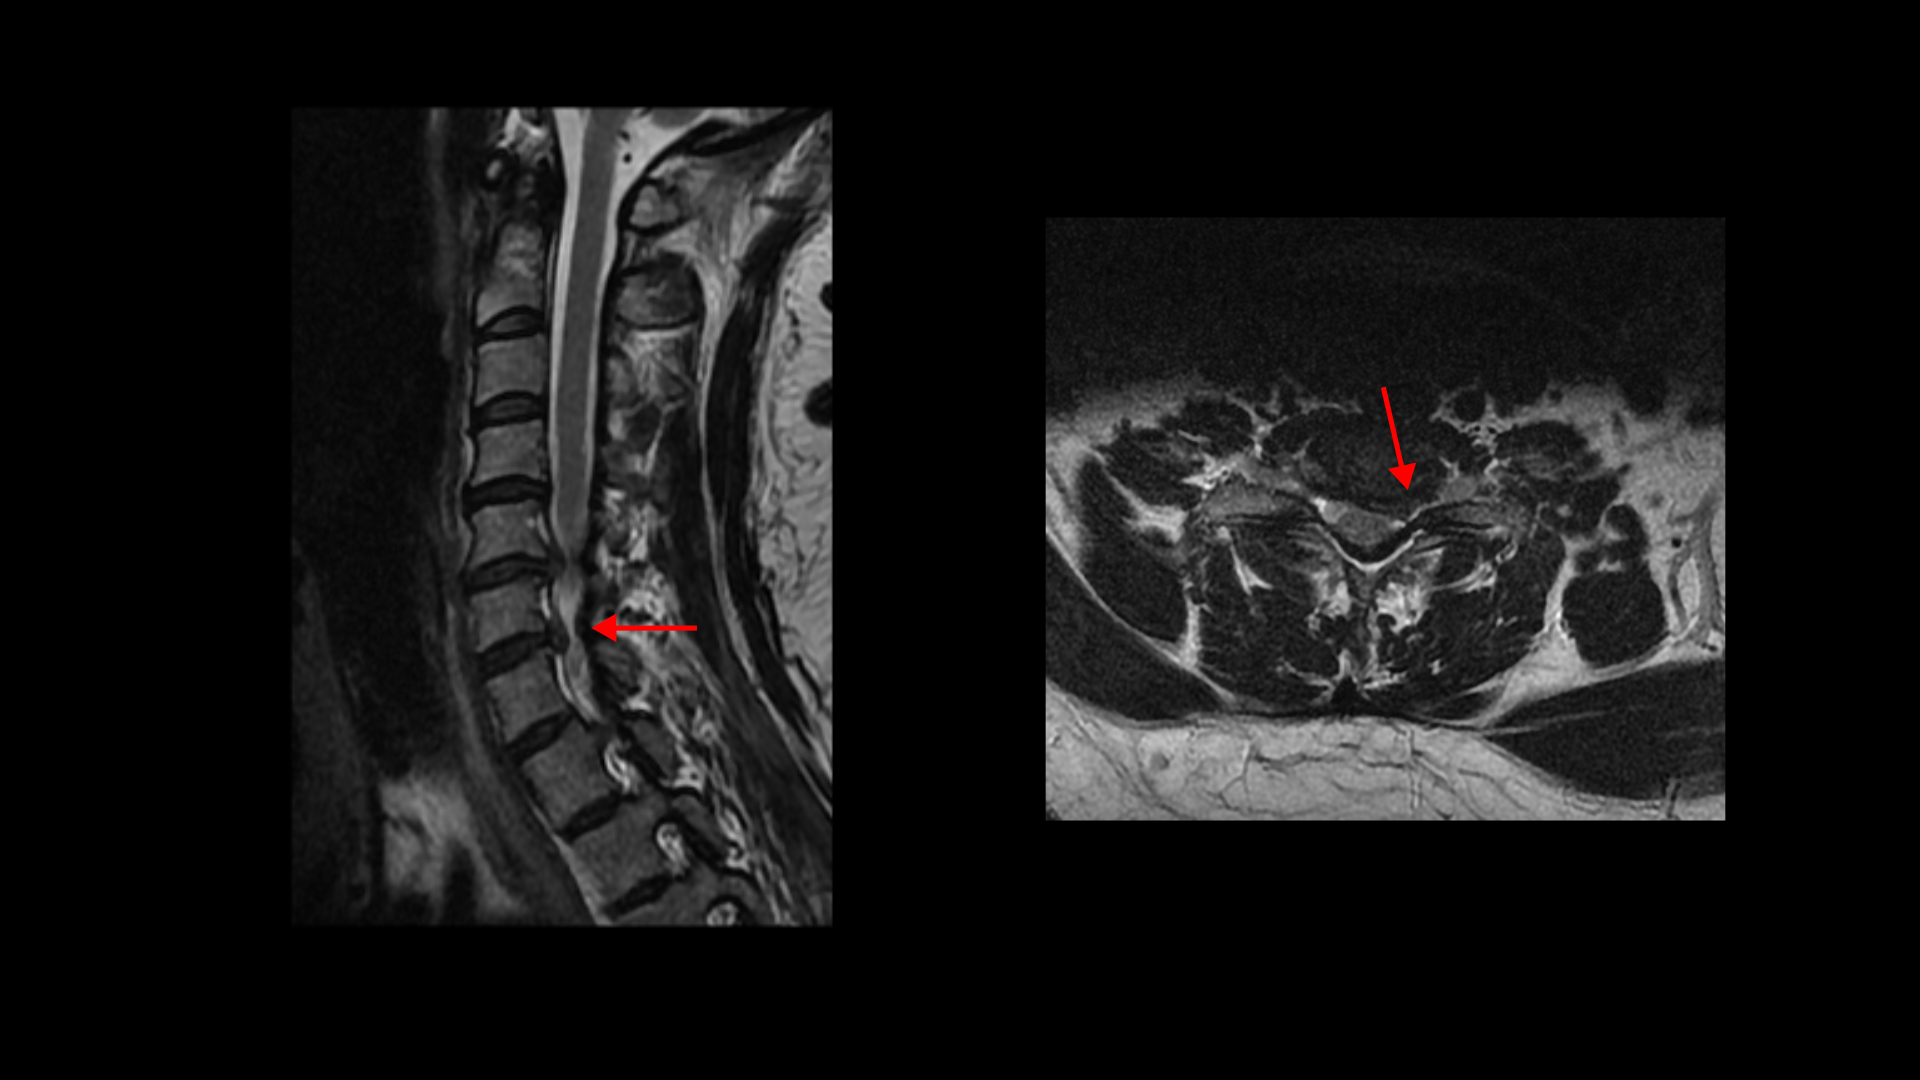

이분 MRI를 보면 목디스크 5번 6번과

6번 7번 두 마디가 왼쪽으로 심하게 밀려 나와 있습니다.

이렇게 심하게 밀려 나와 있으니까 왼쪽 팔의 통증과 함께 마비도 있고 앉거나 일어서면 목의 커브가 조금씩 변하면서 신경을 더 눌러, 앉기도 서서 걷기도 어려운 겁니다.